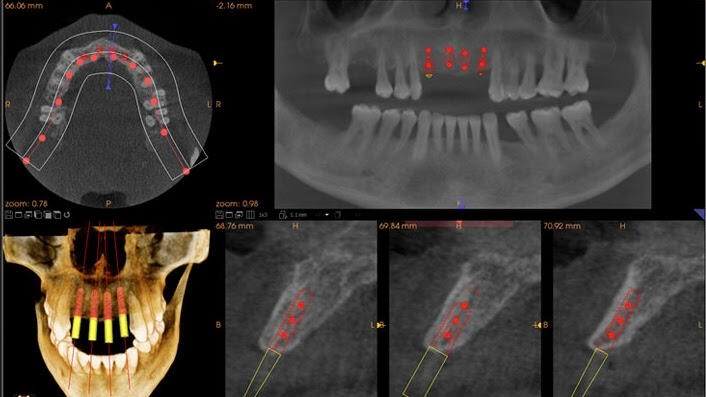

Some patients have complicated conditions that require additional information to safely plan and successfully treat. Fortunately, technology is available in our office that delivers a complete 3-Dimensional image of the jaws in just seconds. The 3D Cone Beam Computed Tomography (CBCT) is the newest and most advanced kind of imaging in dentistry. Our in-house dental CT saves you the time and expense of additional trips to other specialty clinics.

When necessary we use 3D imaging to make decisions about more complicated dental care such as:

- Evaluations for implants